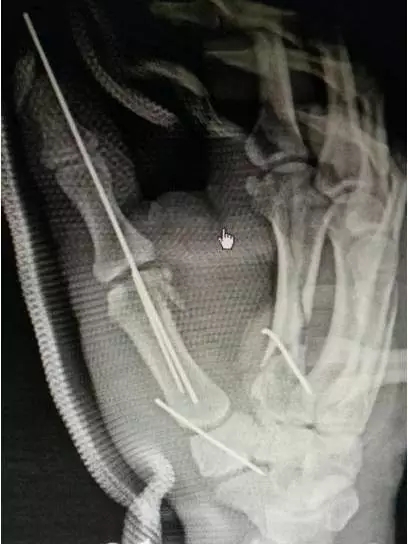

麻醉、反复消毒、反复清创、骨折内固定、铺设VSD海绵辅料、放置VSD负压吸引........由马忠超主任带领的外科手术团队,紧张而又有序的忙碌着,在经过3个多小时的努力奋战,小吴的第一次手术顺利完成。